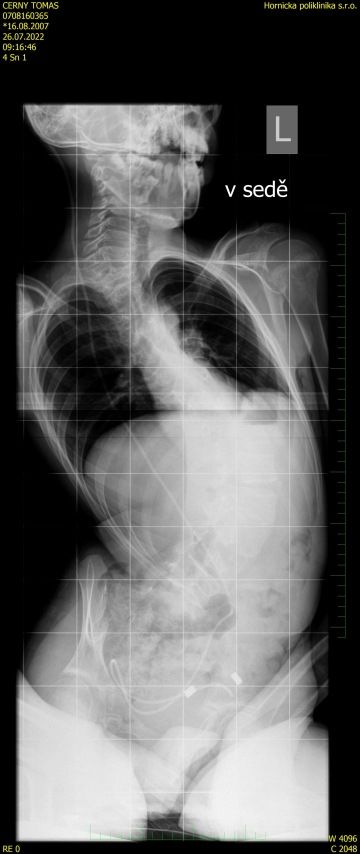

V posledních třech letech se u Tomáše zhoršuje skolióza páteře, která dosáhla děsivých 123 stupňů. Operace, která by mu pomohla, je bohužel příliš riskantní kvůli jeho dalším diagnózám. Tomík proto potřebuje speciální vozík na míru, který mu zajistí pohodlí a podporu a zároveň mu umožní aktivně trávit čas venku.